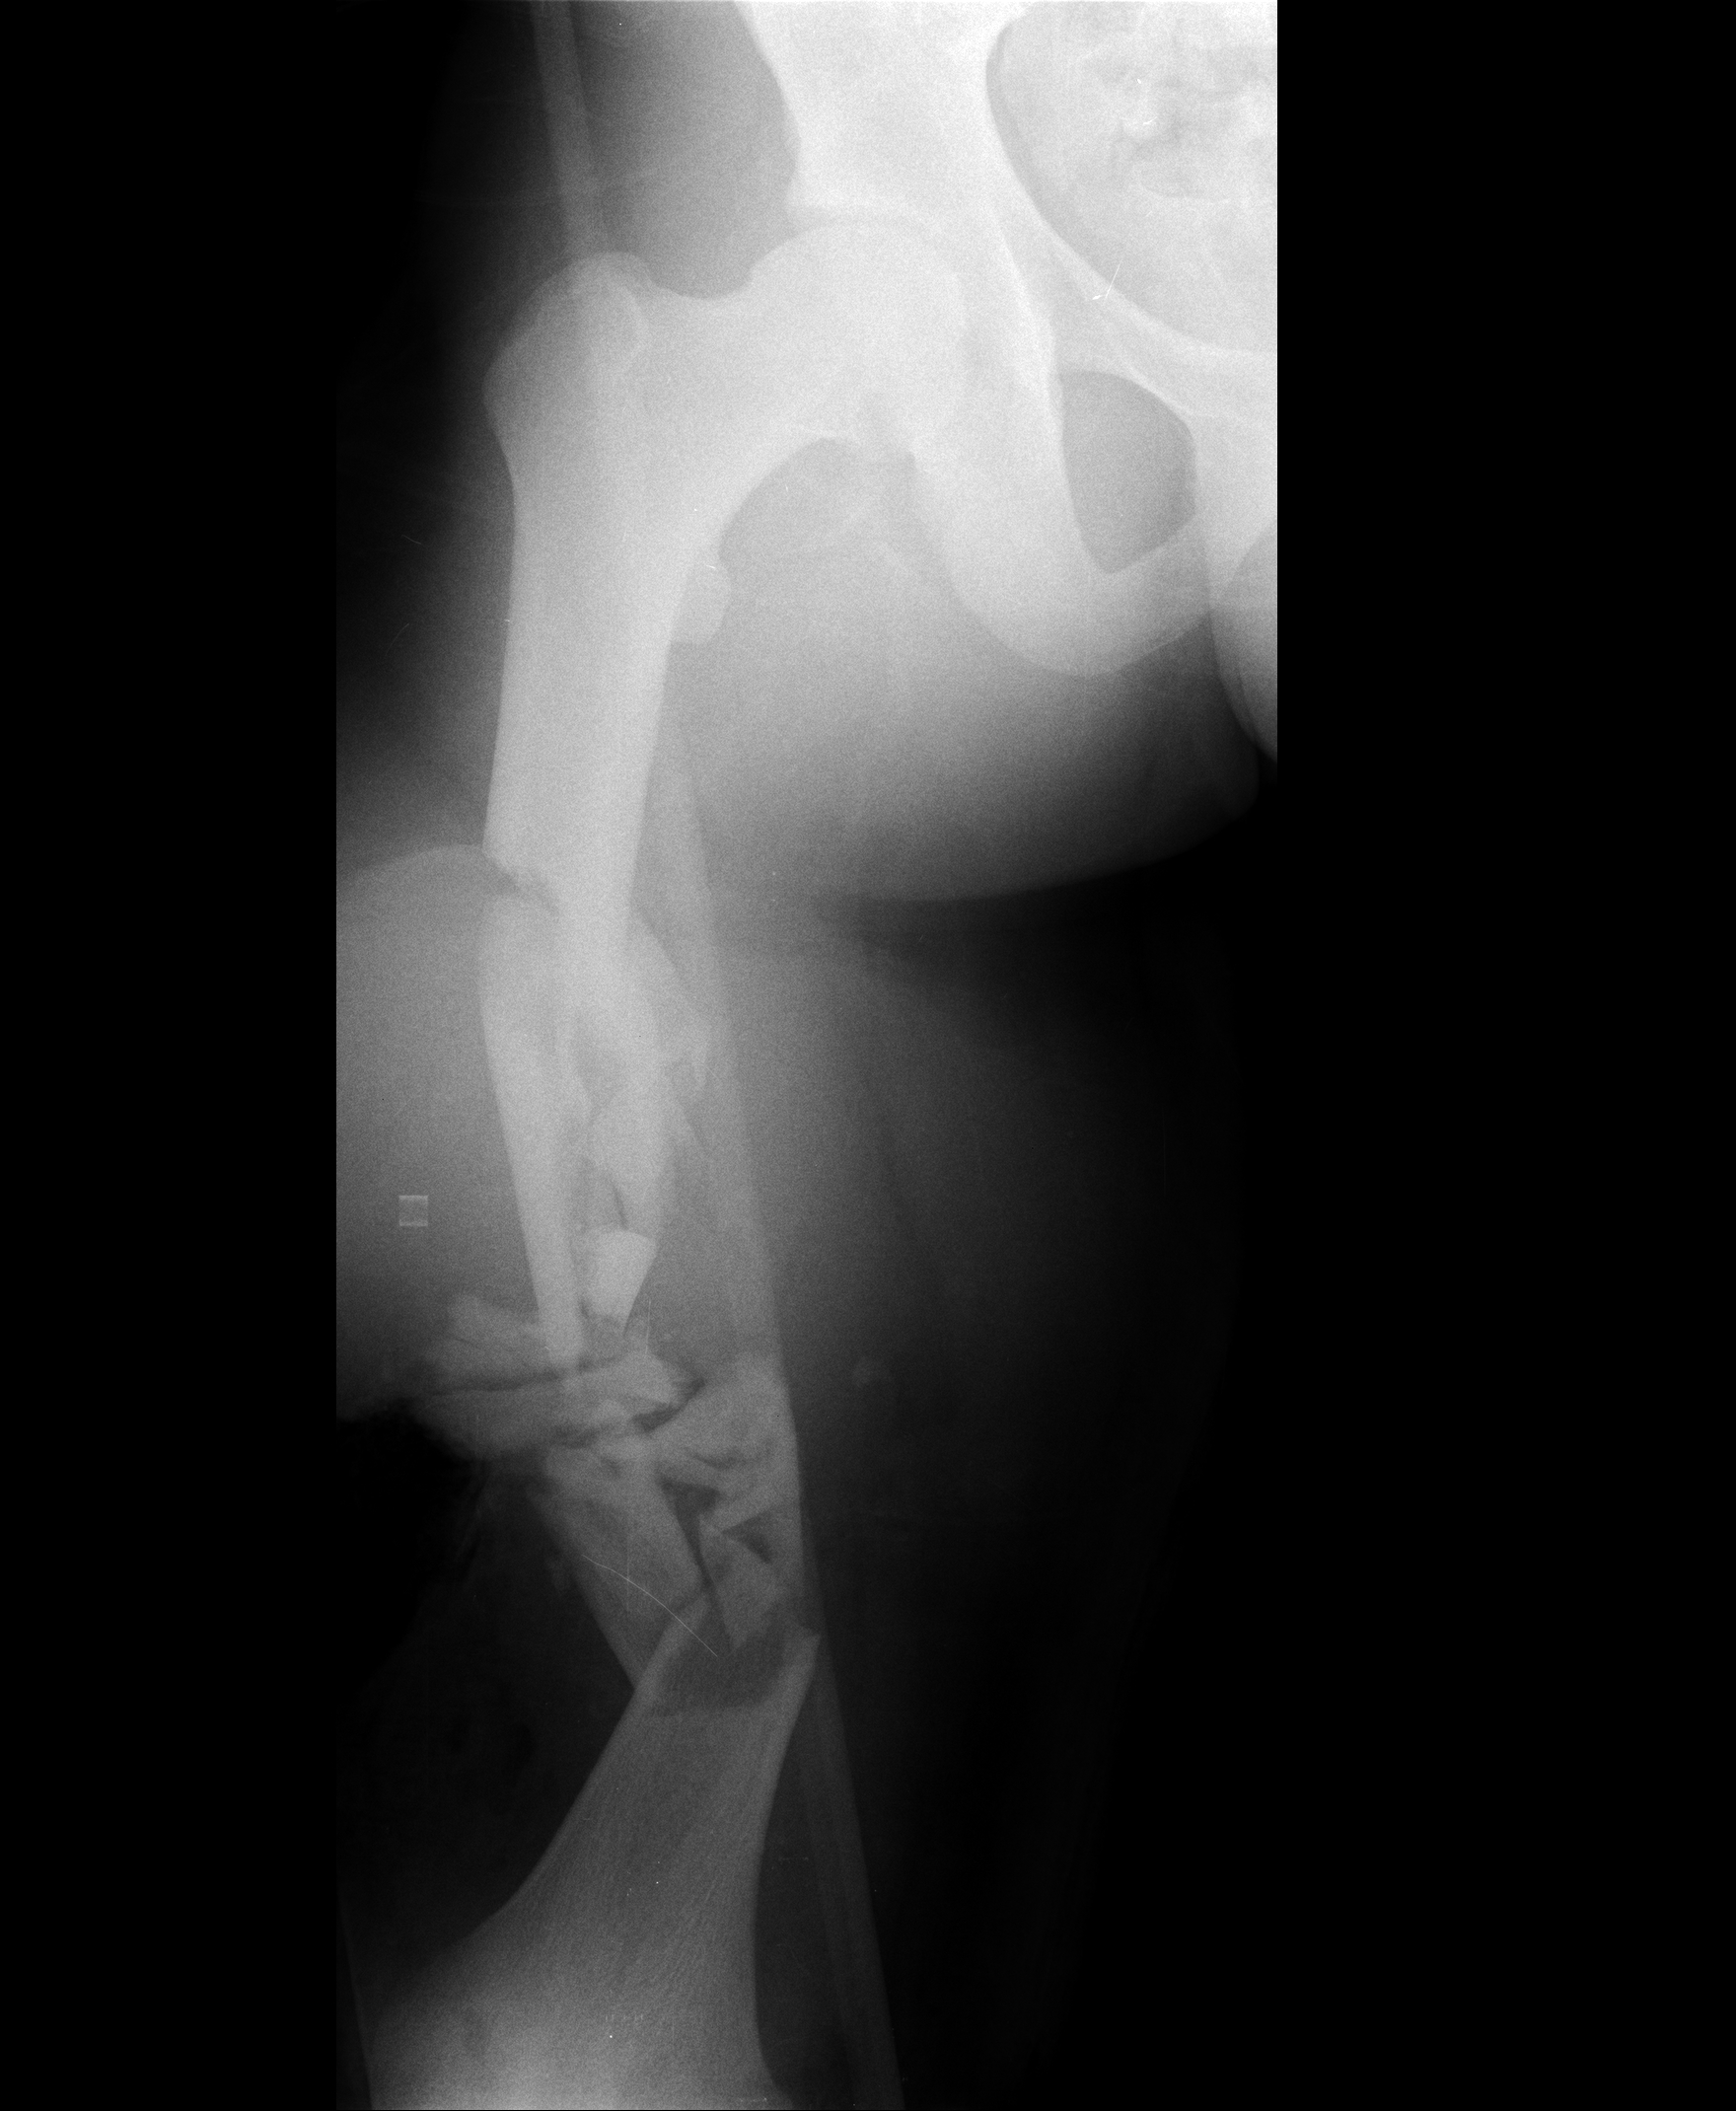

Neste estudo, os pacientes sofreram traumas graves, com perdas ósseas e de partes moles, realizaram múltiplas cirurgias e tiveram longos períodos de reabilitação, e apesar de tudo isso alcançaram bons resultados. Acredita-se que este resultado também esteja relacionado com o início precoce do programa de reabilitação. No paciente que apresentou melhor resultado (Figura 1), observou-se consolidação óssea, com hipertrofia significativa da fíbula, amplitude de movimento da articulação do joelho em 110° e marcha com uso de bengala para meio externo, devido a sua insuficiência do mecanismo extensor do joelho. Portanto, atingiu uma recuperação funcional adequada, onde consegue realizar atividades como subir e descer escadas sem dificuldades e conseguiu retornar ao mercado de trabalho.

Figura 1 - Radiografia de um dos pacientes do estudo. a: raio-x inicial com fratura de fêmur. b: fíbula vascularizada implantada 1 ano após o trauma. c: 6 anos após a fíbula vascularizada com consolidação óssea evidente